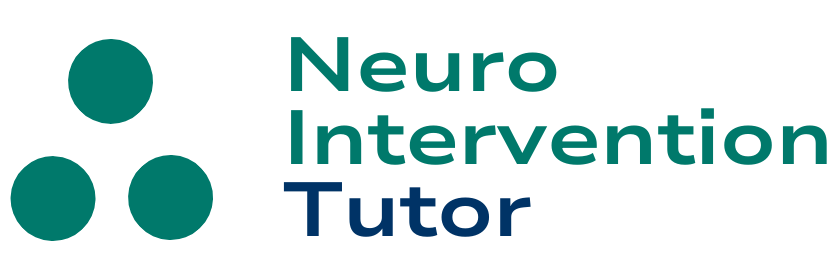

Example of another way to attack an ACOM — feasible when both A1 and A2 branches at least ~1.5 mm in diameter. Bilateral A1 to A2 flow diverter implantation can be technically challenging but ultimately effective

Run through the Phenom 027 after PED deployment, 2.5×12.

Post deployment there is no longer preferential supply of the right side via the left A1